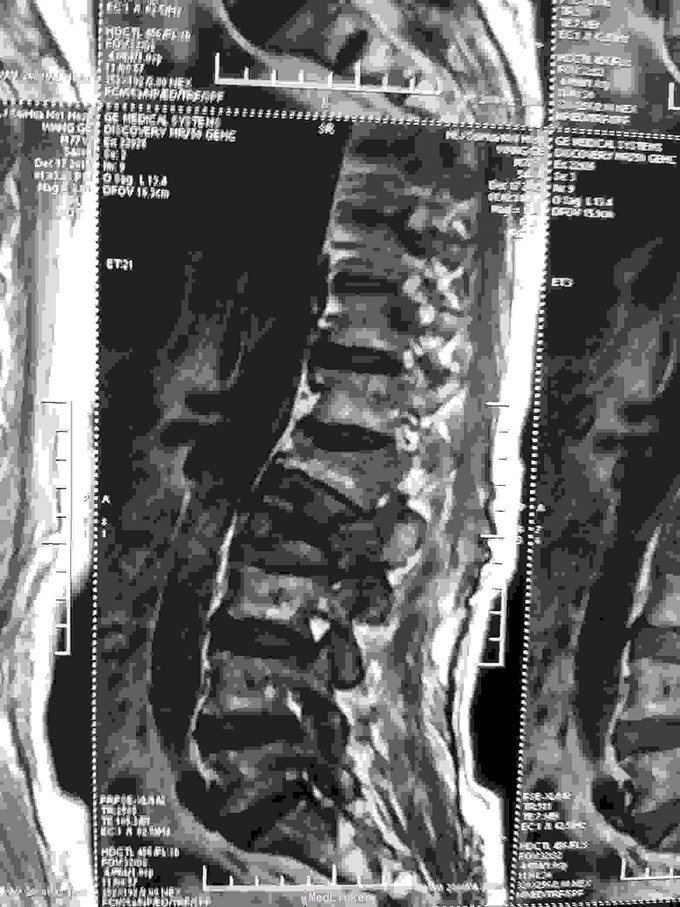

患者老年男性,77岁。因:腰痛,伴双下肢放射痛。活动受限二天。来诊。病人近半年间断腰痛,休息减轻。劳累加重。近二日腰背部疼痛明显加重。不能平卧于床。行走困难。双下肢放射痛。急来诊。因不能平卧,无法查核磁共振,门诊以:腰间盘突出收入院。

查体:神志清,语言流利。呼吸平稳。腹软,腰背部外形较好,无畸形。不能平卧,屈伸活动受限。床上取侧身蜷腿弯腰卧位。双侧下肢放射痛。肌力减退。皮肤感觉麻木。无辅助检查。

根据病史查体诊断:腰间盘突出症待确诊。应用消肿营养神经镇痛治疗。一天。查核磁共振示:腰椎多节段间盘突出伴椎管狭窄。第二腰椎骨破坏侵及椎板。部分突入椎管,脊髓受压。诊断:腰间盘突出伴椎管狭窄。第二腰椎转移癌,脊髓受压。经与家属沟通,查双肺CT:双肺下叶炎症。肺部纤维化。可见肿瘤阴影。肋骨及胸膜受累。胸椎部分骨破坏。最终诊断:双肺癌,胸椎,腰椎骨转移,脊髓受压。多节段腰椎间盘突出。病人至肿瘤科治疗。